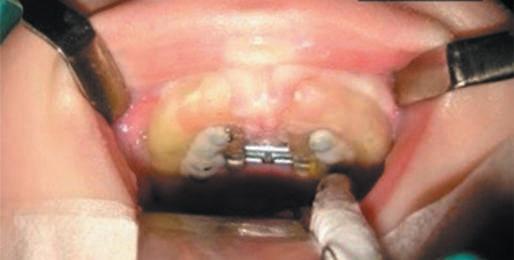

Descrição Técnica

1. Moldagem da arcada superior do neonato realizada com silicone de condensação (Perfil, Vigodent, RJ) e moldeiras de acrílico perfuradas e customizadas. O modelo de gesso (tipo III, Asfer, SP) é isolado com Cel-Lac (SS White, RJ), e sobre ele é confeccionado um dispositivo em acrílico, contendo um parafuso expansor (Morelli Orthodontics, SP) e duas placas de osteossíntese (titânio, 1,5 mm) fixadas lateralmente ao parafuso expansor (Fig. 1-5).

Fig. 1-5. dispositivo em acrílico contendo um parafuso expansor (Morelli orthodontics, sP) e duas placas de osteossíntese (titânio, 1,5 mm) com quatro furos e parafusos expansores de 6,5 a 9 mm, fixadas lateralmente ao parafuso expansor.

2. O posicionamento das placas de osteossíntese no aparelho é planejado com base na TC, prevendo a fixação no palato na projeção da parede medial da maxila, com angulação precisa para evitar danos aos germes dentários. São utilizadas placas com quatro furos e parafusos expansores de 6,5 a 9 mm, dependendo da amplitude de expansão necessária.

3. A instalação do dispositivo é realizada sob anestesia geral, intubação orotraqueal fixada à esquerda para cirurgiões destros e à direita para canhotos. O paciente é posicionado em decúbito dorsal, com hiperextensão cervical.

4. Os miniparafusos de 16 mm são inseridos no palato perpendicularmente, na projeção planejada (Fig. 1-6).

Fig. 1-7. Momento de retirada do dispositivo em bloco cirúrgico após fases ativa e passiva da expansão maxilar.

1-8. (a) Pré-operatória e (b) pós-retirada de dispositivo de expansão rápida de maxila à direita.

5. O procedimento tem tempo médio de 15 minutos.

6. Não há uso de balões, stents, splints, incisões, ressecções ou descolamento de tecidos.

7. A fase ativa da expansão inicia 24 horas após a cirurgia, com protocolo de 1/4 de volta duas vezes ao dia, durante aproximadamente 18 dias. A interrupção da fase ativa baseia-se em critérios clínicos e avaliação nasoendoscópica.

8. A fase passiva, de contenção, dura 45 dias, visando à consolidação óssea e reorganização da sutura maxilar (Fig. 1-7).

9. Ao final da expansão, nova TC pode ser realizada para mensuração objetiva do ganho de espaço aéreo (Fig. 1-4), além da avaliação clínica (Fig. 1-8).